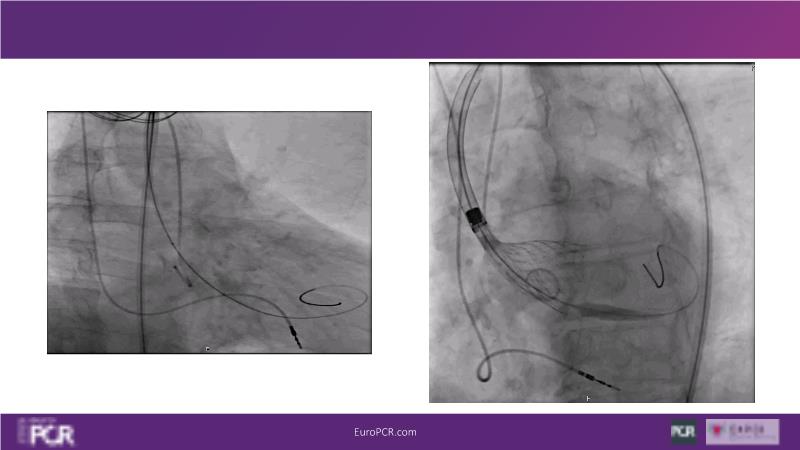

Watch this session to discover insights into patient-prosthesis mismatch and strategies to mitigate risks, delve into the significance of aortic valve commissure for coronary alignment optimization during TAVI, and explore solutions for common TAVI challenges such as peripheral vessel tortuosity and asymmetric valve calcifications in large or small aortic annuli.

- To discuss options to overcome common daily challenges of TAVI: peripheral vessel tortuosity, horizontal aorta, asymmetric valve calcifications in large, or in small aortic annuli